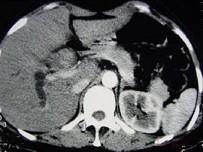

问题 女,35岁,右上腹痛1月,黄疸进行性加重,AFP阴性,消瘦乏力,影像检查如图,最可能的诊断为()

选项 A.肝转移癌 B.胆管癌 C.局灶性脂肪肝 D.原发性肝癌 E.肝血管瘤

答案 B